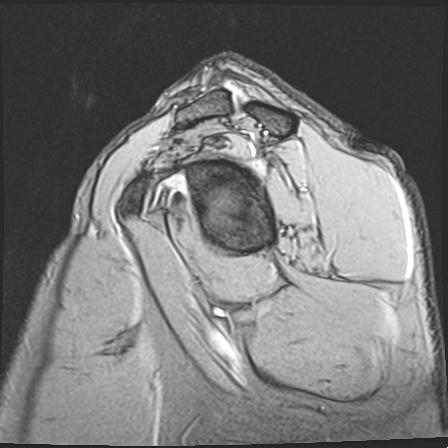

60058 3/9 11/4 右肩 2R+MRI 73歳男性 肩腱板損傷